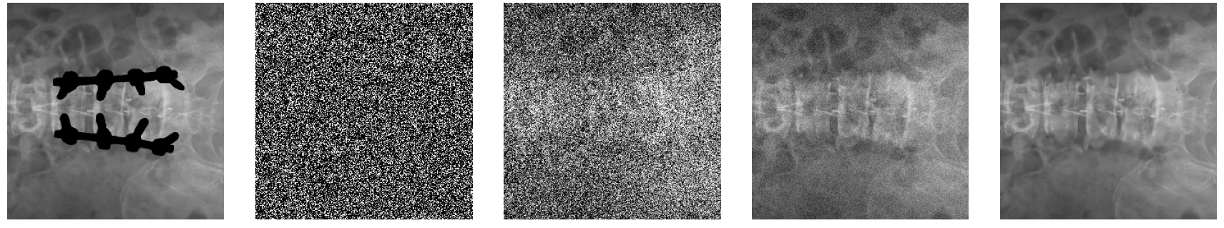

The diffusion model gradually reconstructs coherent anatomical structures from noise. Starting from a fully noisy state, the model iteratively refines the masked region over approximately 1000 timesteps.

From left to right: masked input, noisy state (t≈1000), intermediate steps (t=100, t=10), and final reconstruction (t=0).